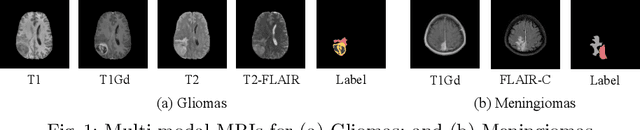

Figure 1 for NestedFormer: Nested Modality-Aware Transformer for Brain Tumor Segmentation